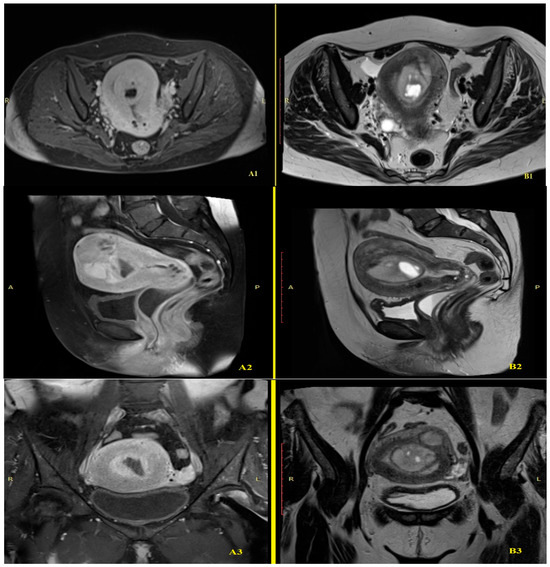

2.2. Imaging Findings